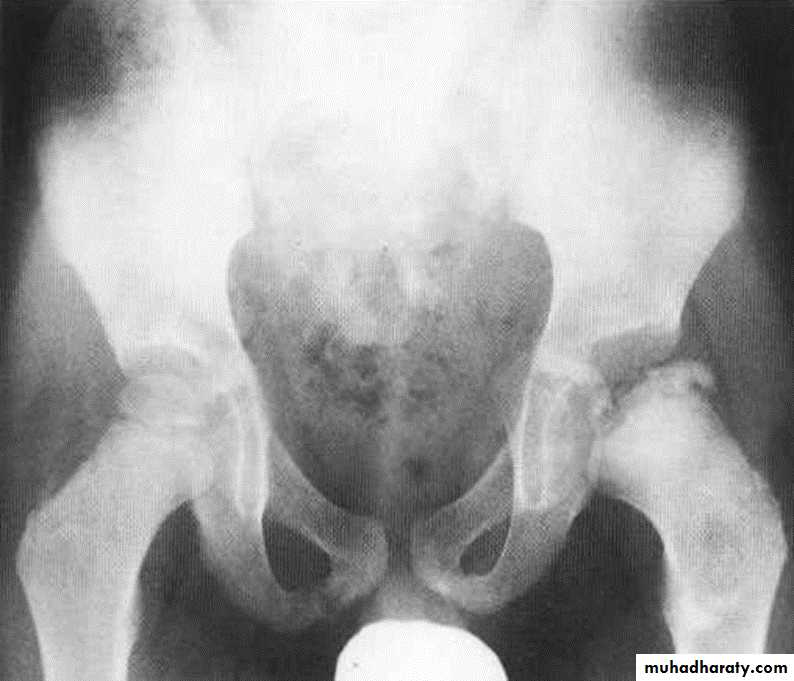

DEVELOPMENTAL DYSFLASIA OF HIP (CONGENITAL DISLOCATION OF THE HIP)

An abnormally lax joint capsule allows the femoral head to fall out of the acetabulum, leading to deformation.

CDH occurs most commonly (70%) in the left hip. Bilateral involvement is seen in 5%.

Radiographic features:

6 months and later

* AP veiw ( femural epiphysis are visualized ):* Superolateral displacement of proximal femur (disturbed shenton’s line )

* Increase in acetabular angle

* Small capital femoral epiphysis

Femoral head is located lateral to Perkin's line

* Other features that are sometimes present

Abnormal sclerosis of the acetabulum

Shallow acetabulum

Formation of a false acetabulurn